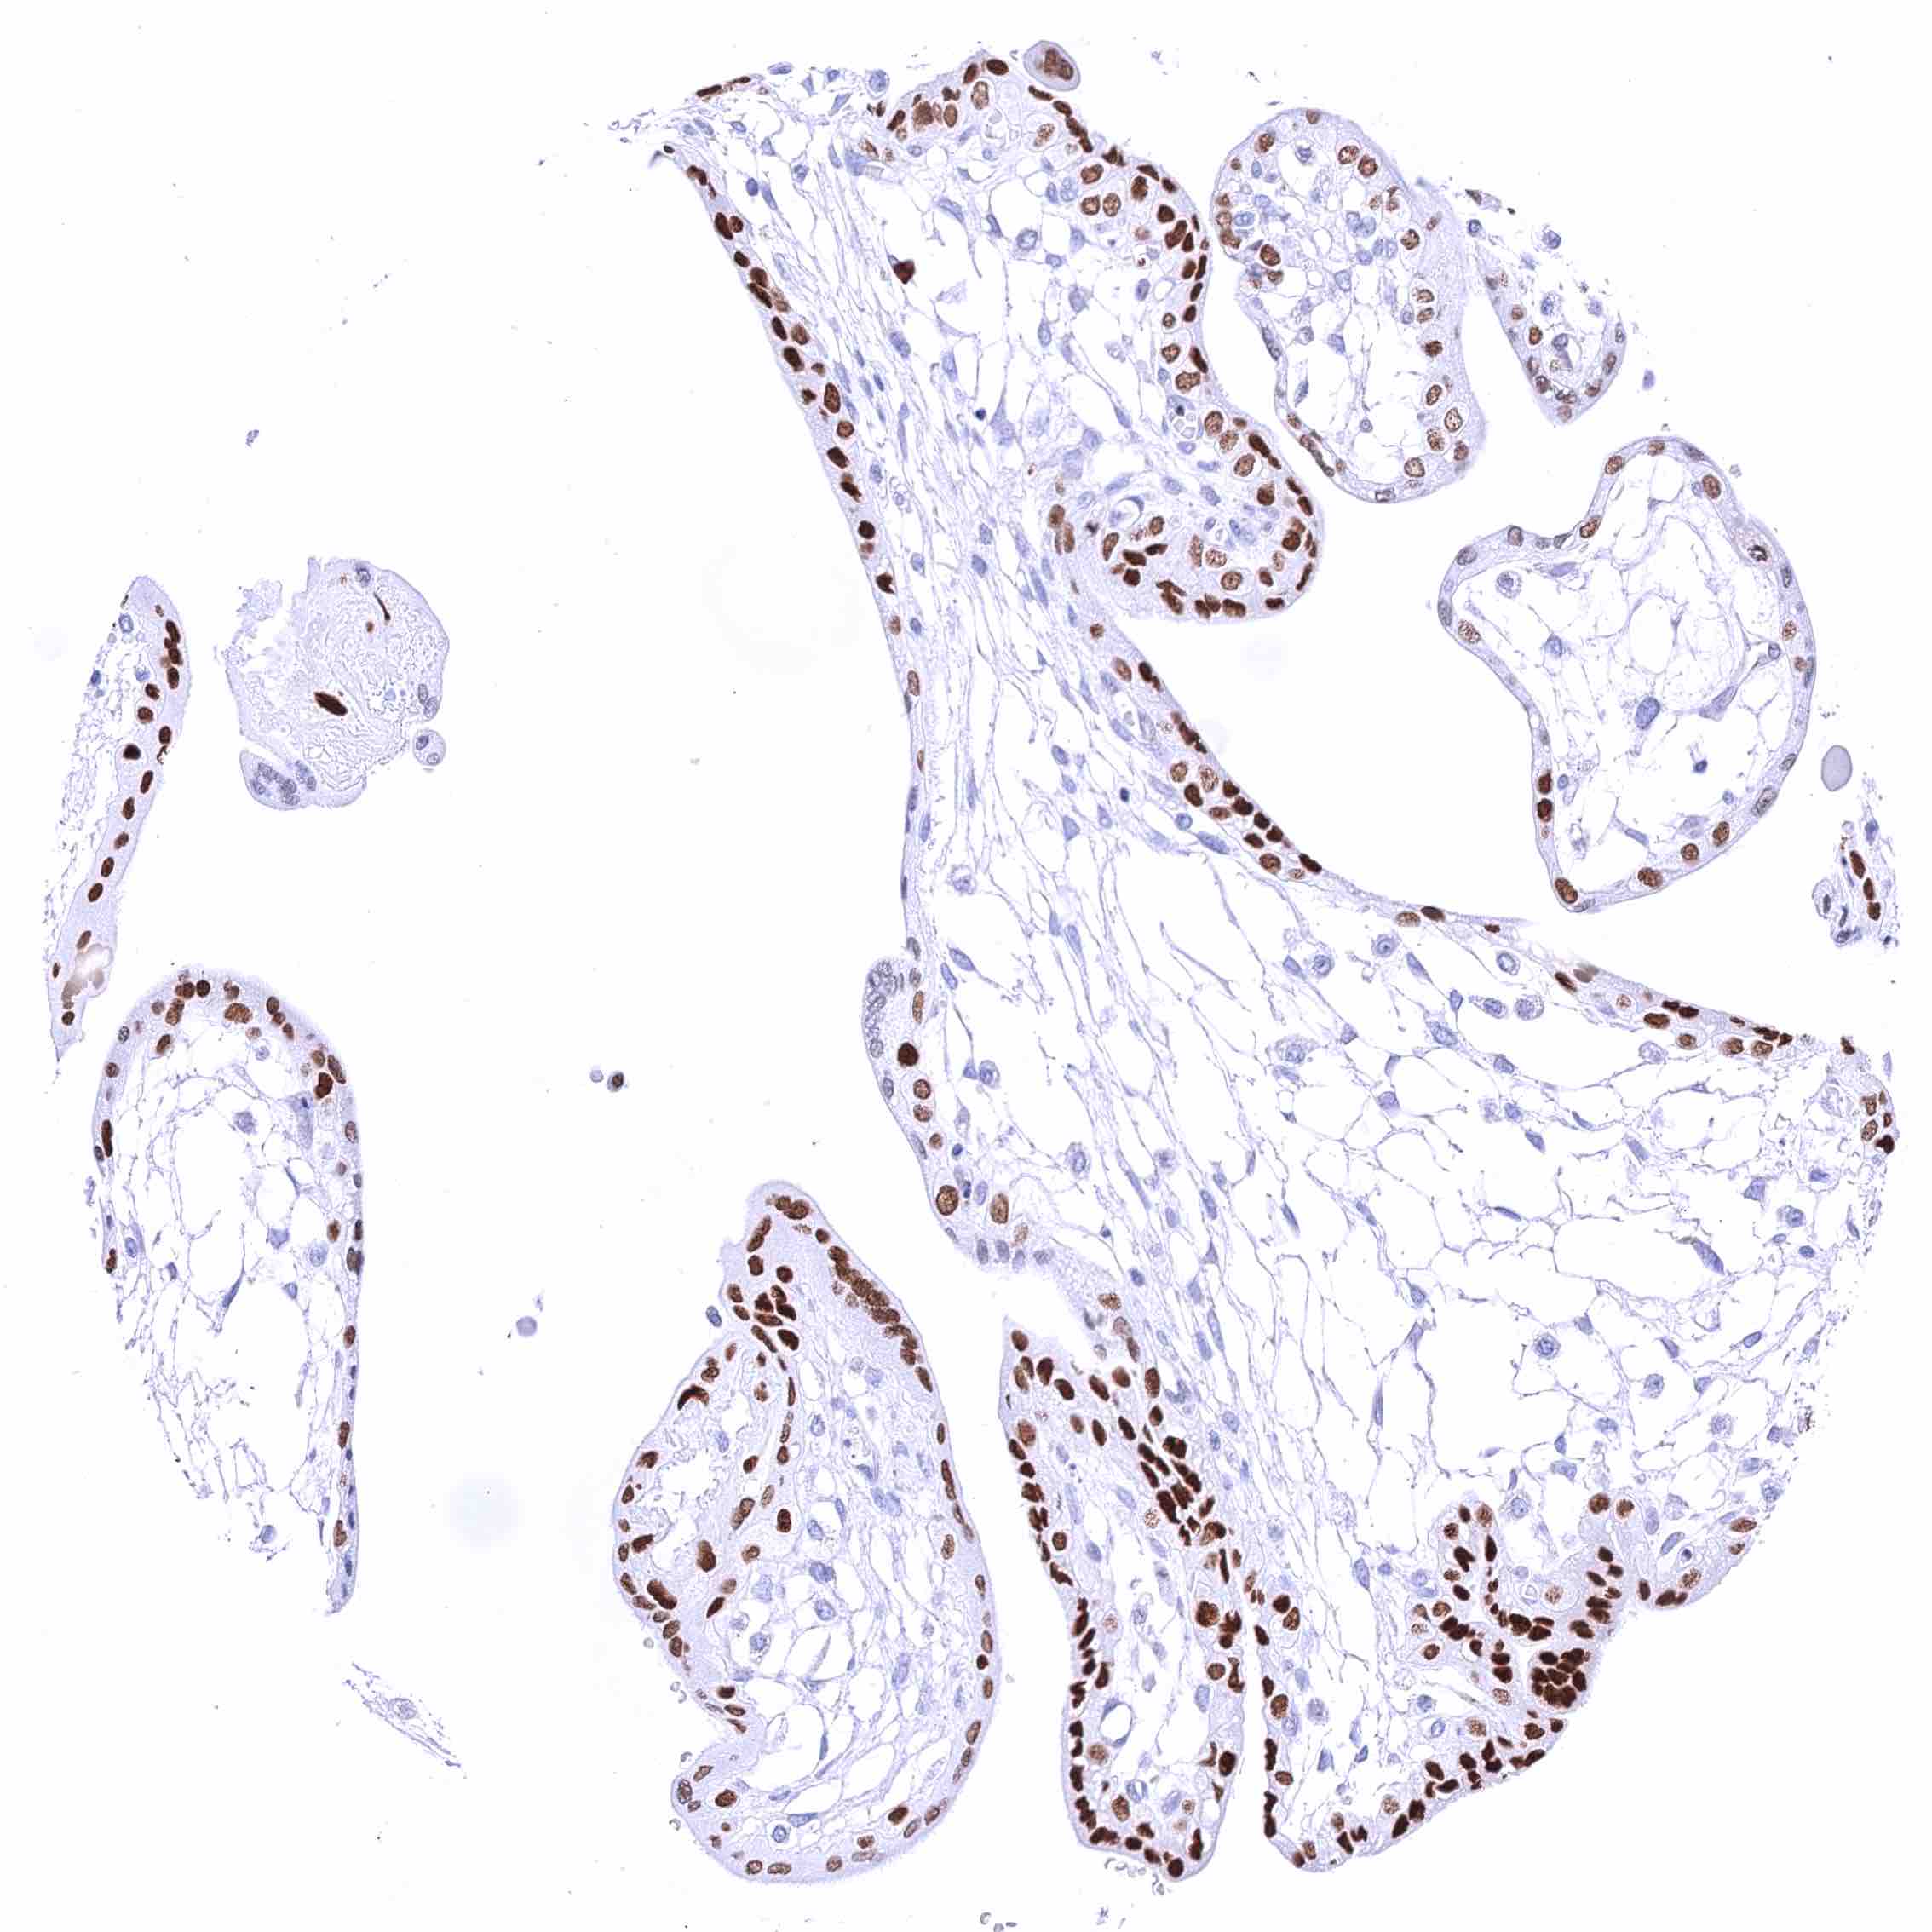

Breast – Moderate to strong GATA3 staining of luminal cells while myoepithelial cells remain GATA3 negative.